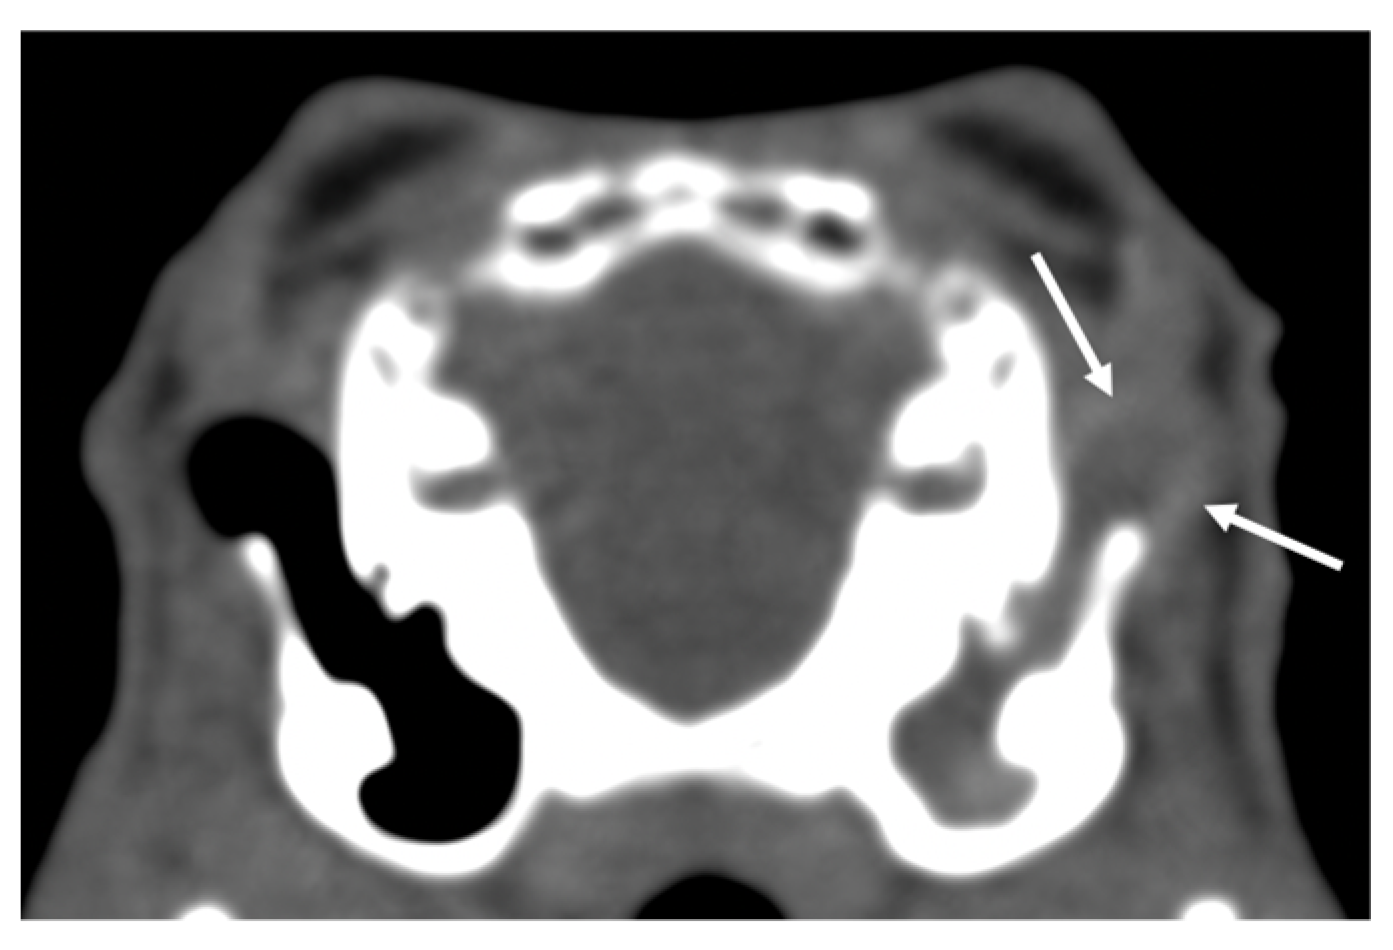

3.1. Rabbits

| Bulla tympanica | Increased attenuation (11/34) | Enlargement (0/0) | Thickening of the wall (6/16) | Lysis or irregularities of the wall (2/0) |

| External ear | Increased attenuation (23/1) | Displacement (0/0) | Aural diverticulosis (9/0) | |